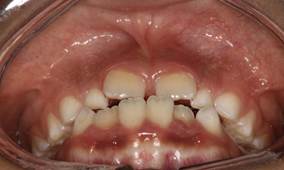

Análisis intraoral: Al observar la boca del paciente nos encontramos que la mucosa está húmeda y lubricada con pigmentación melánica, el frenillo es de inserción mucosa; hay poca inflamación de las encías. El paladar duro es profundo. El paciente está en dentición mixta, existe una mordida cruzada anterior con apiñamiento en el sector anteroinferior. En el arco superior se observa un diastema entre los incisivos centrales superiores permanentes, también se observa que estos dientes están ligeramente rotados. La relación molar de ambos lados es de clase III y la relación de los caninos deciduos también es de clase III.

Fig.3 Fotografía intraoral de frente Fig.

4 Fotografía intraoral de 45°

Fig. 5 Fotografía intraoral lado derecho Fig. 6 Fotografía intraoral lado izquierdo